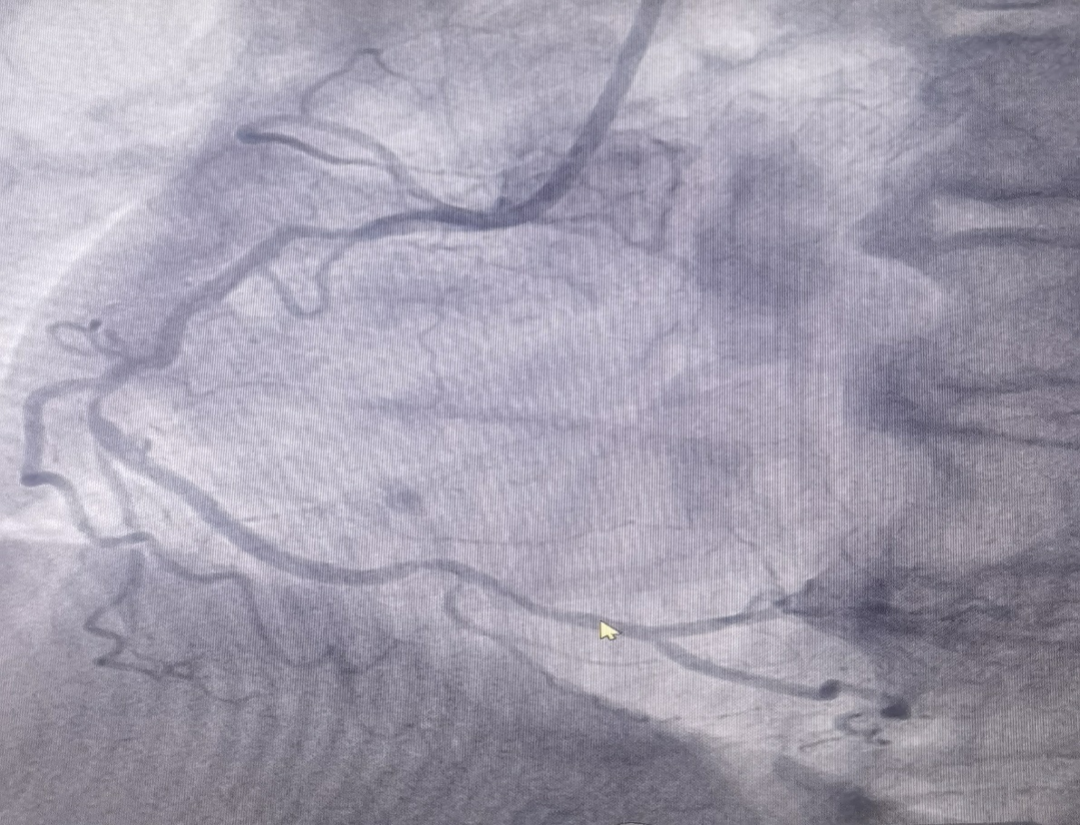

男性患者,72歲,入院診斷為:冠心病,不穩(wěn)定型心絞痛。冠脈造影結果提示右冠脈重度狹窄,考慮為此次發(fā)病的病變血管。

(圖為右冠病變術前影像)